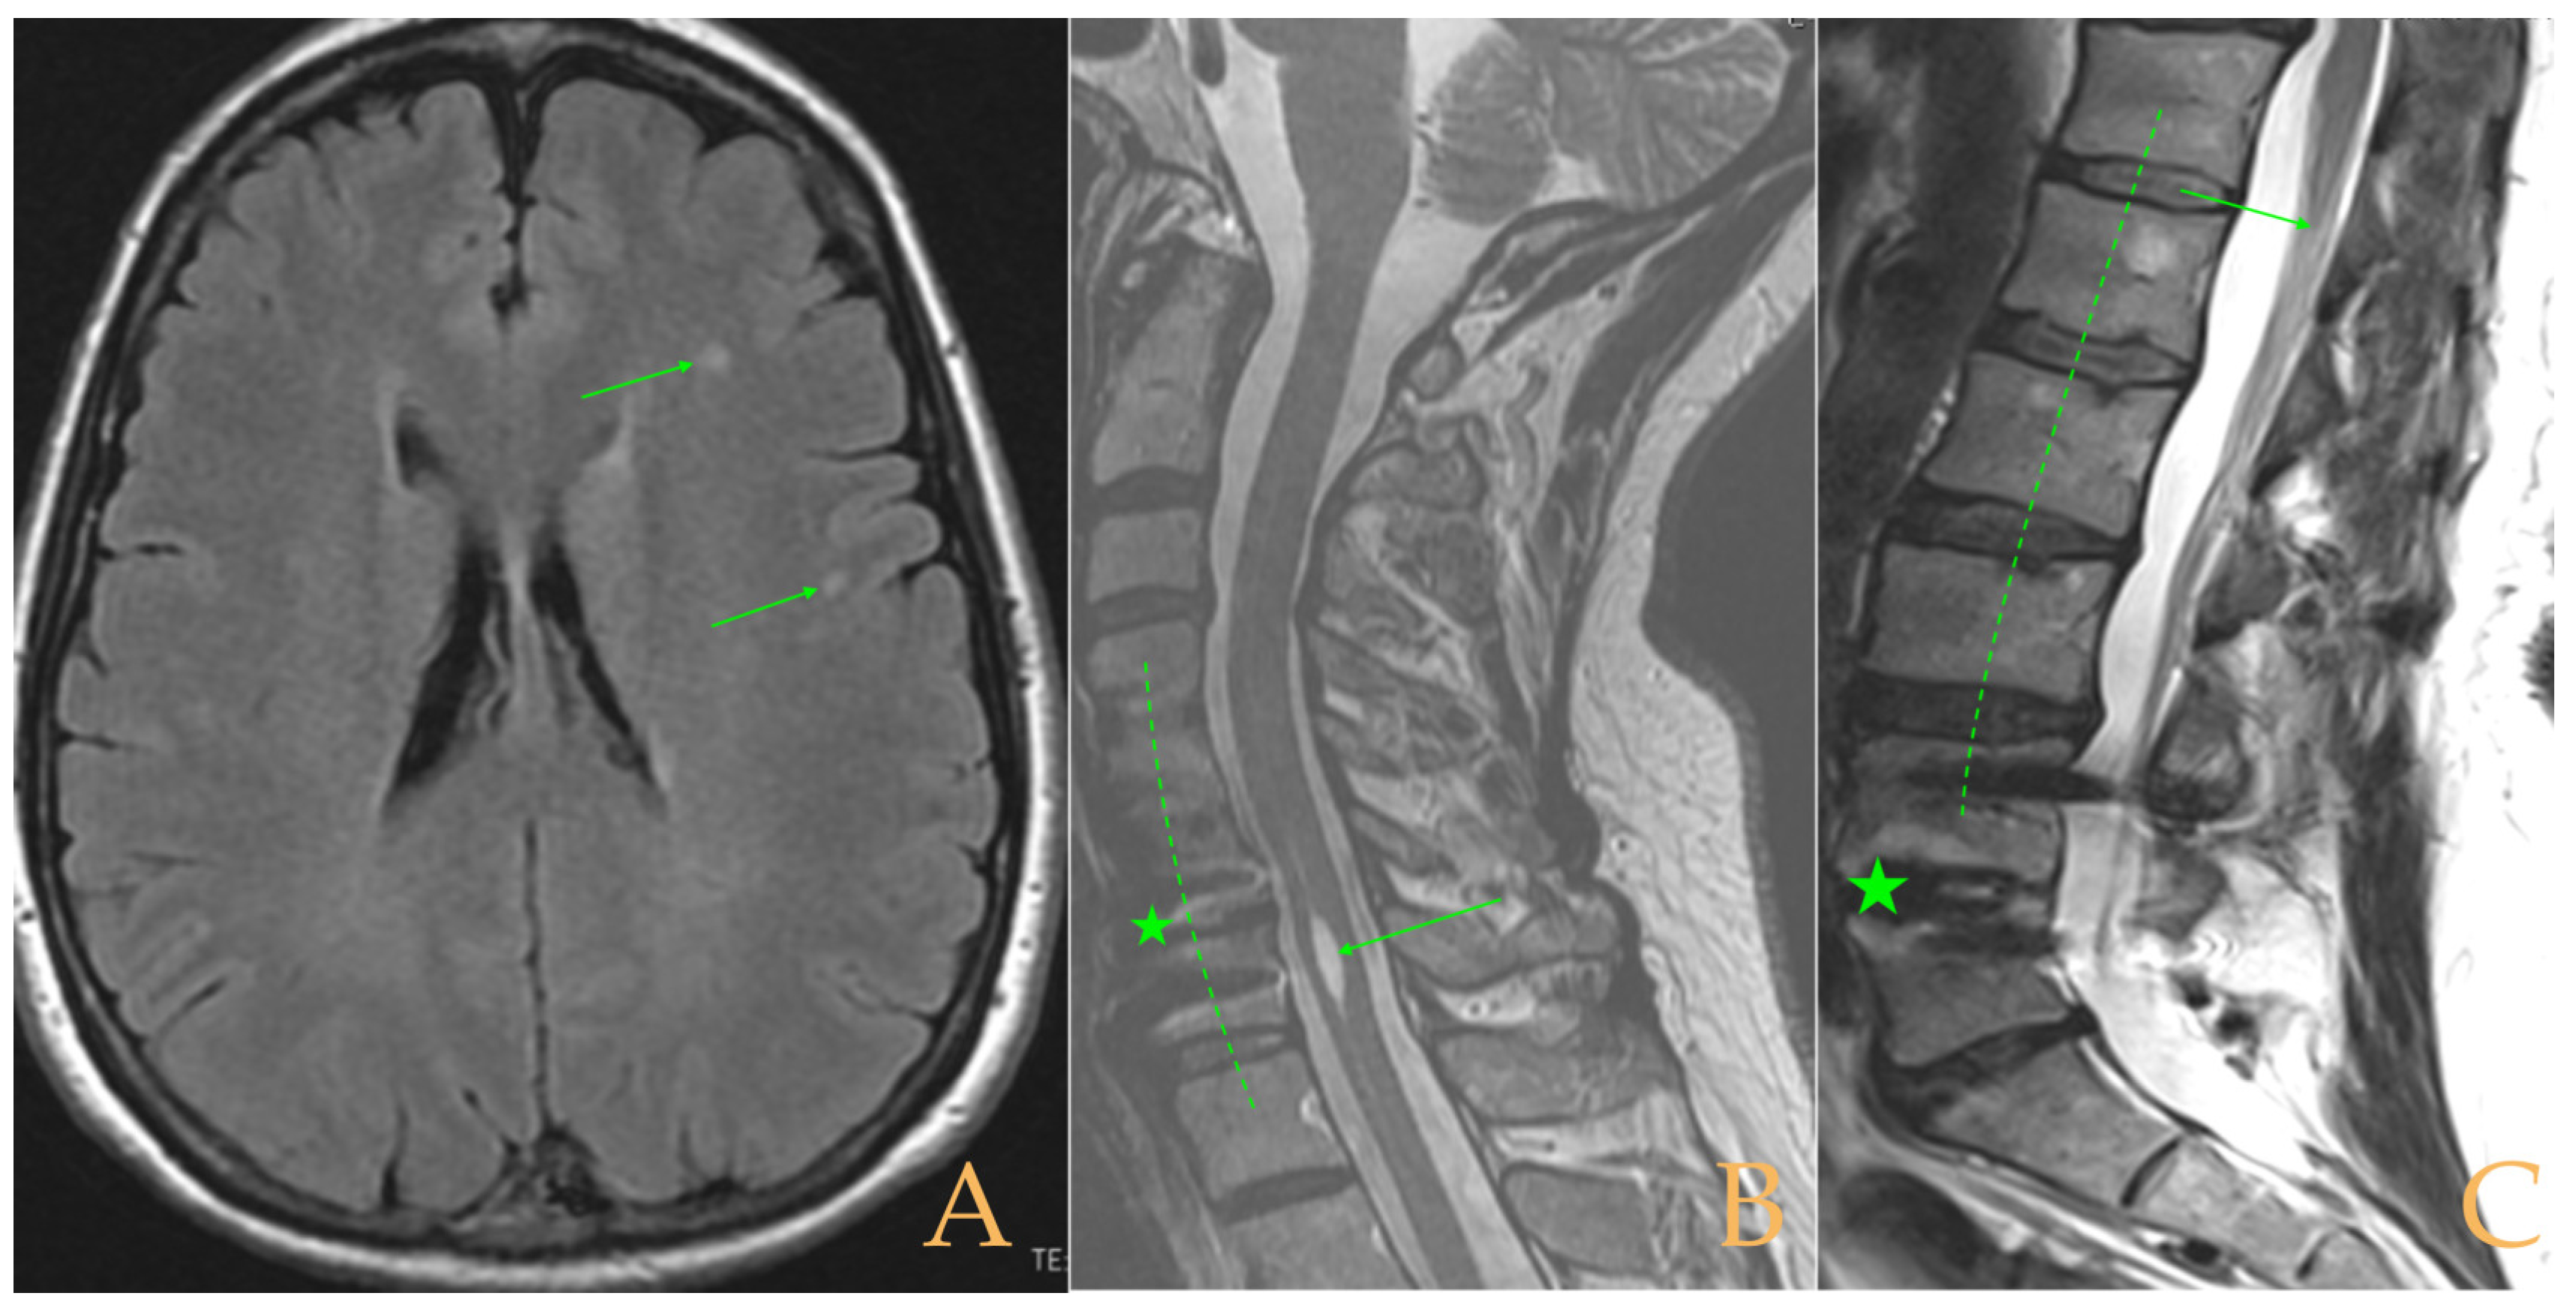

Magnetic resonance imaging showed a slight descent of the cerebellar tonsils, multiple diseased discs, and conus medullaris at the level of the middle third of the L1 vertebra. The X-ray images of the entire spine revealed a mild dextroconvex thoraco-lumbar scoliosis with 5° Cobb angle (Figure 1).

The MRI showed a descent of the cerebellar tonsils, increased supracerebral space, and micro lacunae in the bilateral white matter and the left basal ganglia. Upper cervical kyphosis and straightening in the lower levels. Surgical arthrodesis at C4-C5 and C5-C6. Cervical, thoracic and lumbar protrusions. Ischemia and oedema in the cervical and thoracic spinal cord. Slight cervical rotoscoliosis. Disc protrusions: T7-8, T11-L1, L2-L3-L4, and disc herniation L4-L5. Loss of the lumbar lordosis. Conus medullaris at the level of the middle third of the L1 vertebra (Figure 2). The X-ray images of the entire spine showed levoconvex thoracolumbar scoliosis of 21°, dysmetria of the lower extremities with shortening of the right lower extremity by 10 mm, with respect to the level of the hip, and 99 mm at the level of the iliac crests, 16° cervical lordosis, 49° thoracic kyphosis, and 59° lumbar lordosis.

Figure 2. Imaging of patient 2. A: Image suggestive of spinal cord ischemia (arrows), impaction of the cerebellar tonsils (star), and straightening of the cervical spine (interrupted line); B: straightening of the upper part of the lumbar spine (interrupted line) and conus medullaris at the level of the L2L3 disc space (arrow); and C: brain MRI with micro lacunae in the white matter (arrows).